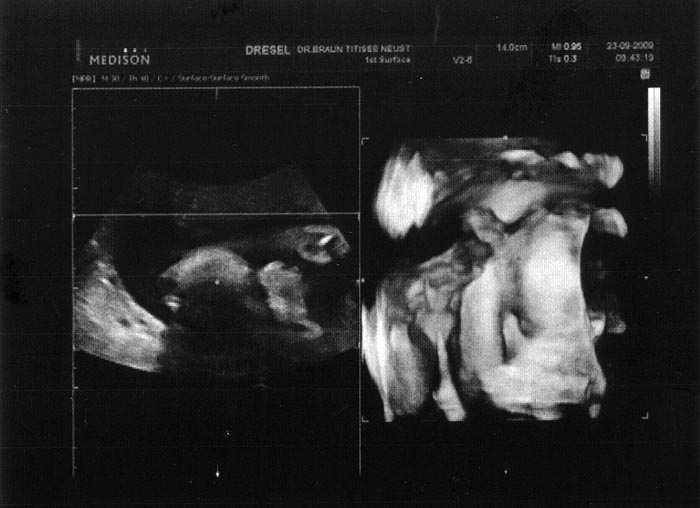

5. Ultraschallaufnahme